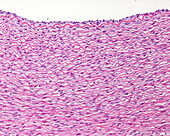

13613497 - Muscular artery wall, light micrograph